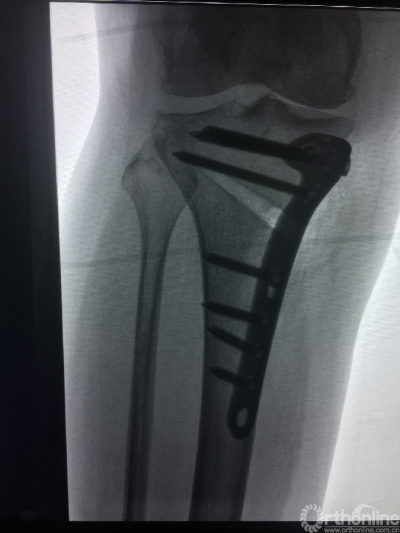

5月27日上午,山西医科大学第二医院骨科关节组副主任医师张民及其手术团队借助3D打印技术,成功为一位55岁的患者实施保膝截骨手术。标志着山西省首台3D打印保膝截骨手术取得成功,此项新技术的开展,为广大骨关节病患者带来了福音,此类疾病患者中逾1/3可终身保有自身关节,不再需要置换人工关节。

患者杨某患双膝骨性关节炎6年,关节变形,疼痛难忍,近几个月病情加重,5月22日到山医大二院骨科就诊。当得知该院可使用3D打印个性化定制截骨导引板进行胫骨平台高位截骨手术,手术时间只需要20多分钟,且费用是置换人工关节的一半。这一技术保留了患者自身的膝关节,术后能完全恢复自身膝关节的生理功能,而且以后还可以继续做农活时,决定接受3D打印截骨手术。

“高位胫骨截骨手术(HTO)已经开展多年,但是,之前由于手术难度高,如果没有精确的角度、深度、斜率等数据为依据,很可能对患者造成骨折及多项病发症,一般都需要具有丰富经验的临床医生才敢实施手术。”通过相关精密设备采集患者数据,并分析制定出个性化手术方案,打印出手术中导引手术角度、深度等6个精准化数据的导板,手术时间缩短了一半以上,且术后患者不仅膝关节疼痛即刻缓解,2-3天左右就可在适当的护膝辅具下,轻踩试走。高位胫骨截骨手术(HTO)最大限度保留患者机体功能,对于术后生活质量要求高及活动度大的患者,成为很好的选择。